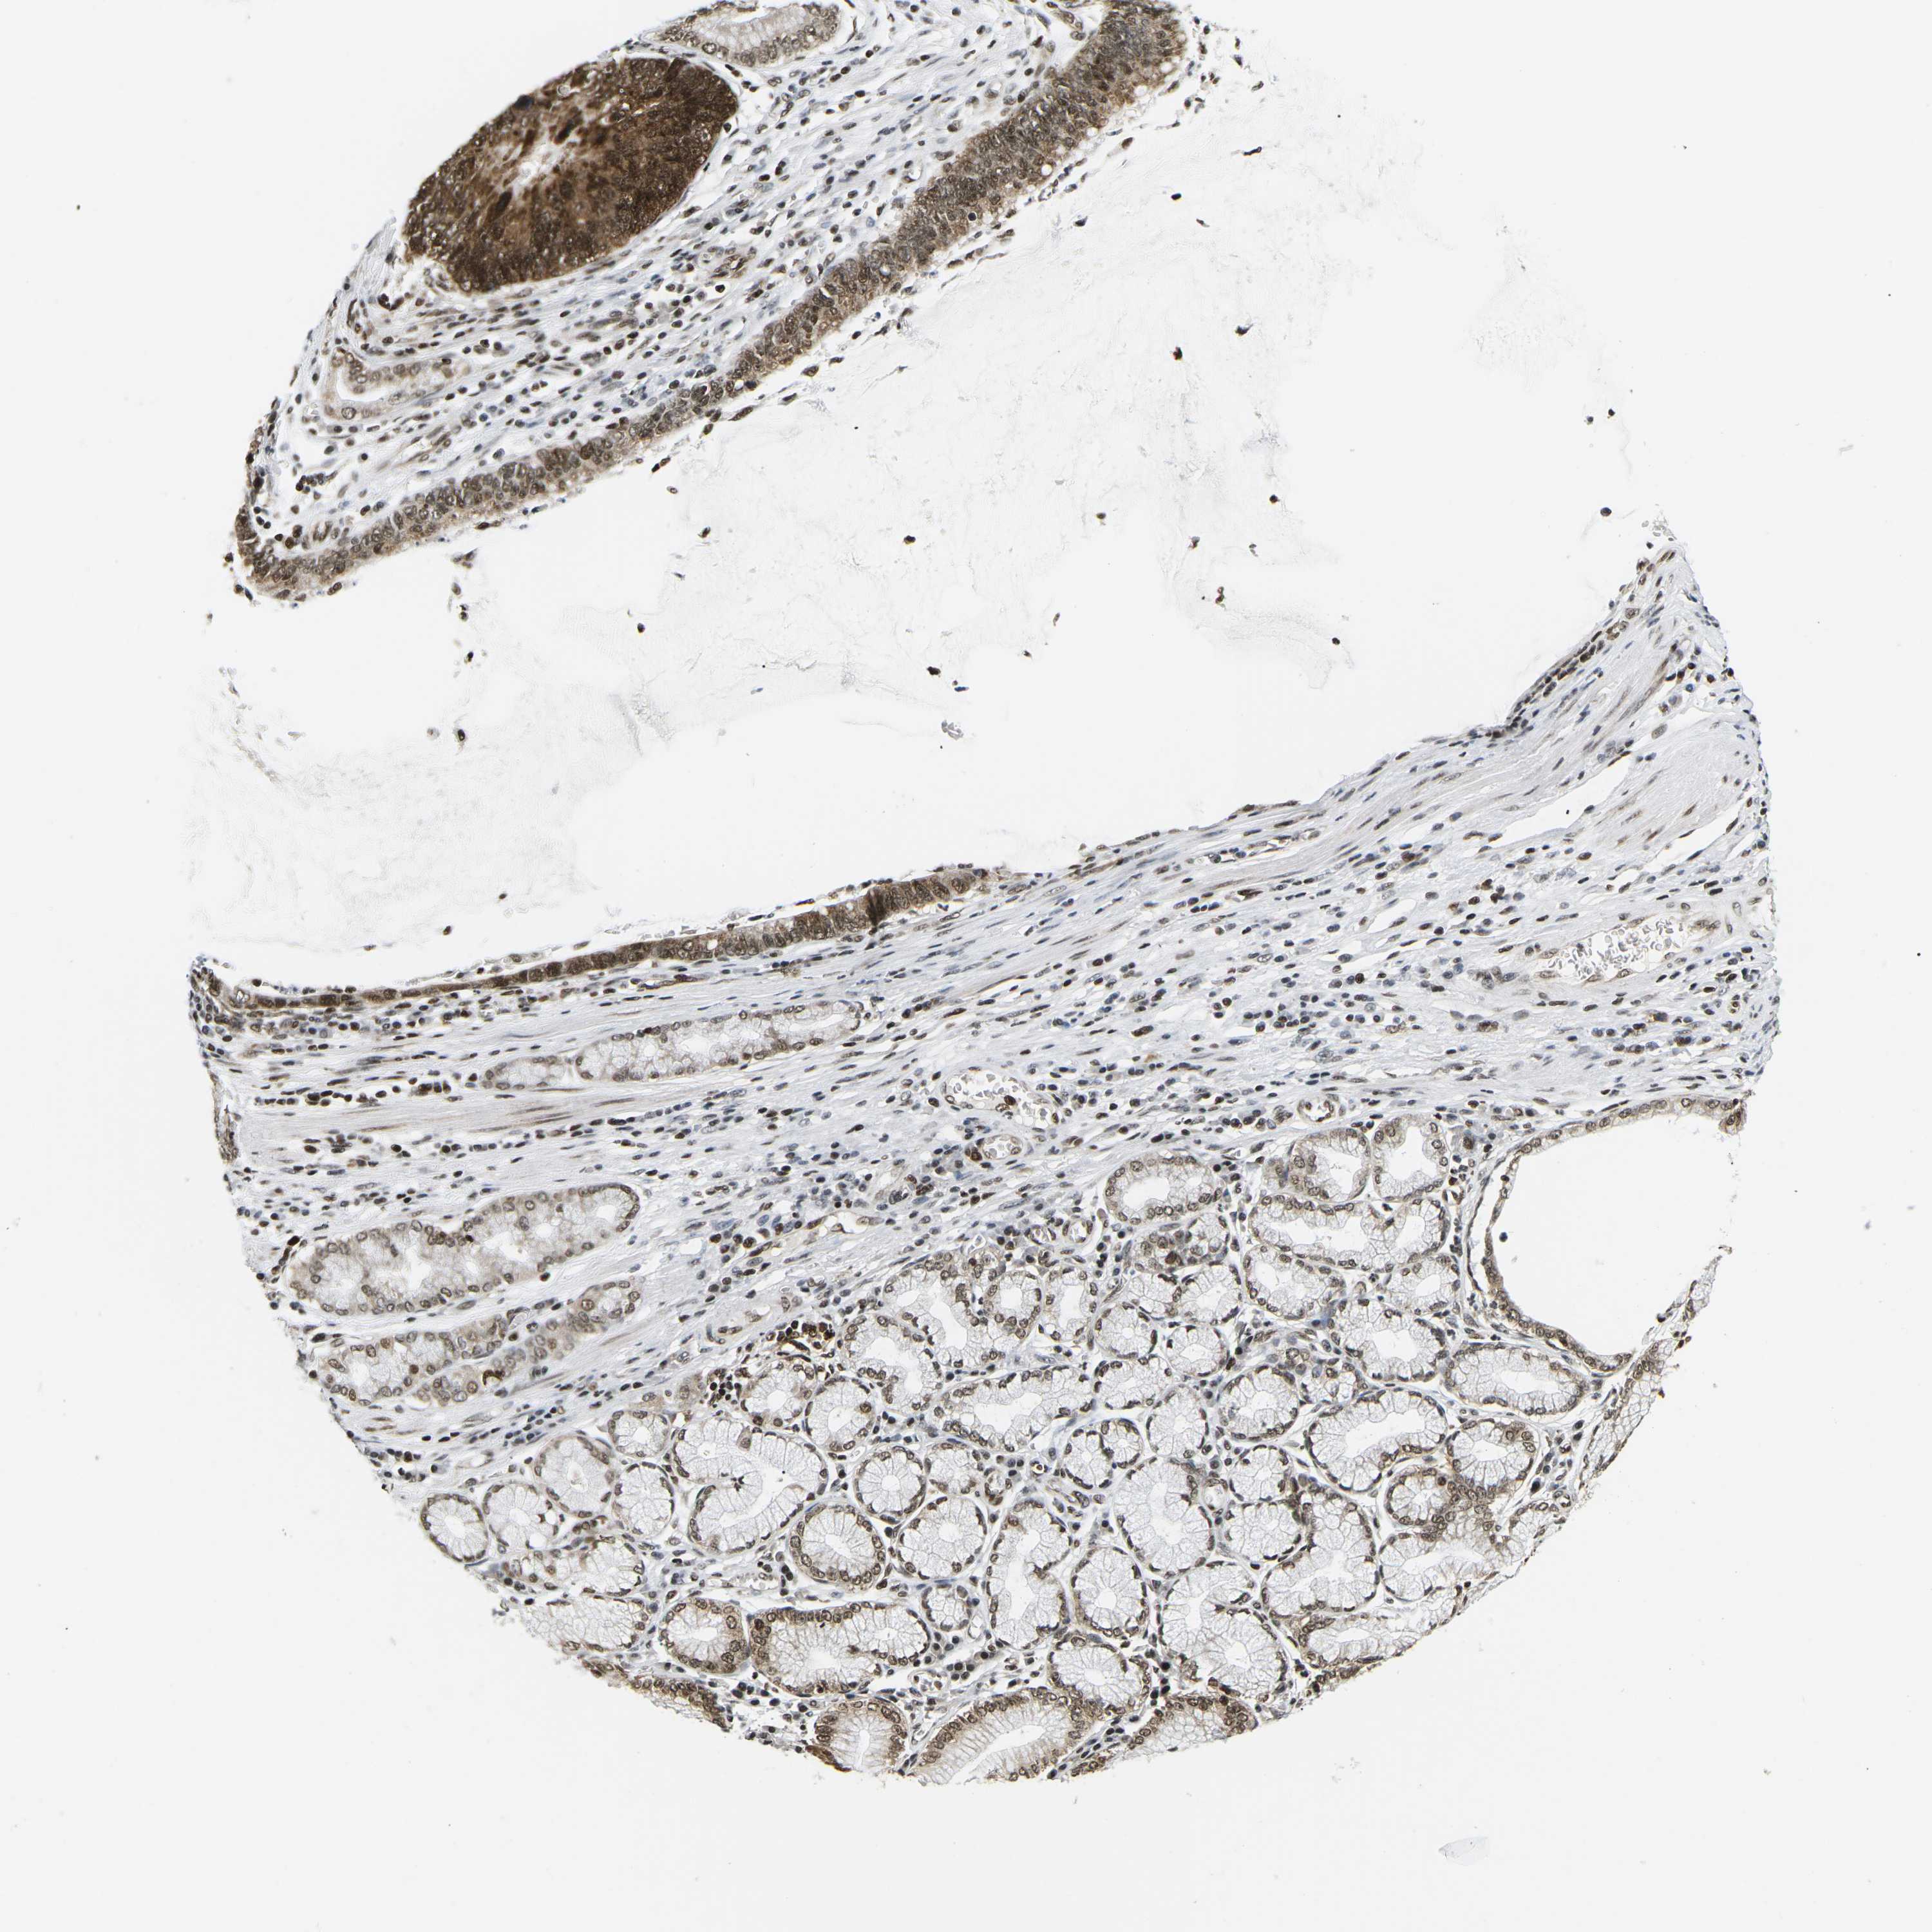

STOMACH CANCER - Protein expressioni

A mouse-over function shows sample information and annotation data. Click on an image to view it in a full screen mode. Samples can be filtered based on level of antibody staining by selecting one or several of the following categories: high, medium, low and not detected. The assay and annotation is described here.

Note that samples used for immunohistochemistry by the Human Protein Atlas do not correspond to samples in the TCGA dataset.

Antibody stainingi

Antibody staining in the annotated cell types in the current human tissue is reported as not detected, low, medium, or high, based on conventional immunohistochemistry profiling in selected tissues. This score is based on the combination of the staining intensity and fraction of stained cells.

Each image is clickable and will lead to virtual microscopy that enables deeper exploration of all samples and also displays staining intensity scores, fraction scores and subcellular localization as well as patient and tissue information for each sample.

Antibody CAB016114

Antibody CAB069989

Staining

High

Medium

Low

Not detected

Intensity

Strong

Moderate

Weak

Negative

Quantity

>75%

75%-25%

<25%

None

Location

Nuclear

Cytoplasmic/membranous

Cytoplasmic/membranous,nuclear

Adenocarcinoma, NOS

Adenocarcinoma, High grade